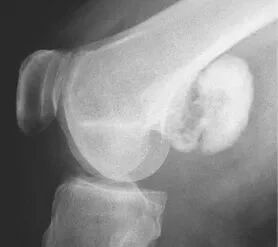

图 12.压迫性骨缺损:骨软骨瘤